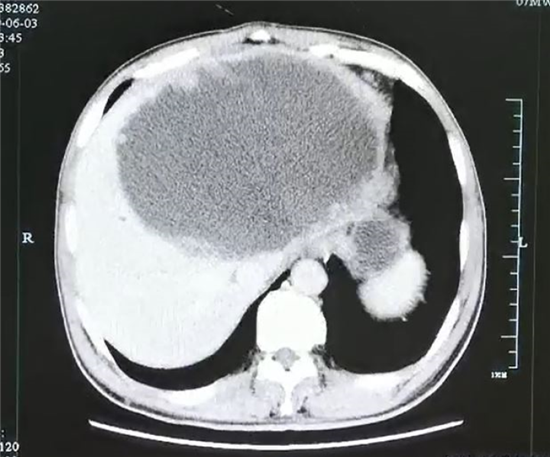

引流前肝脏巨大脓肿,壁厚,且壁上见很多肿瘤样的结构.